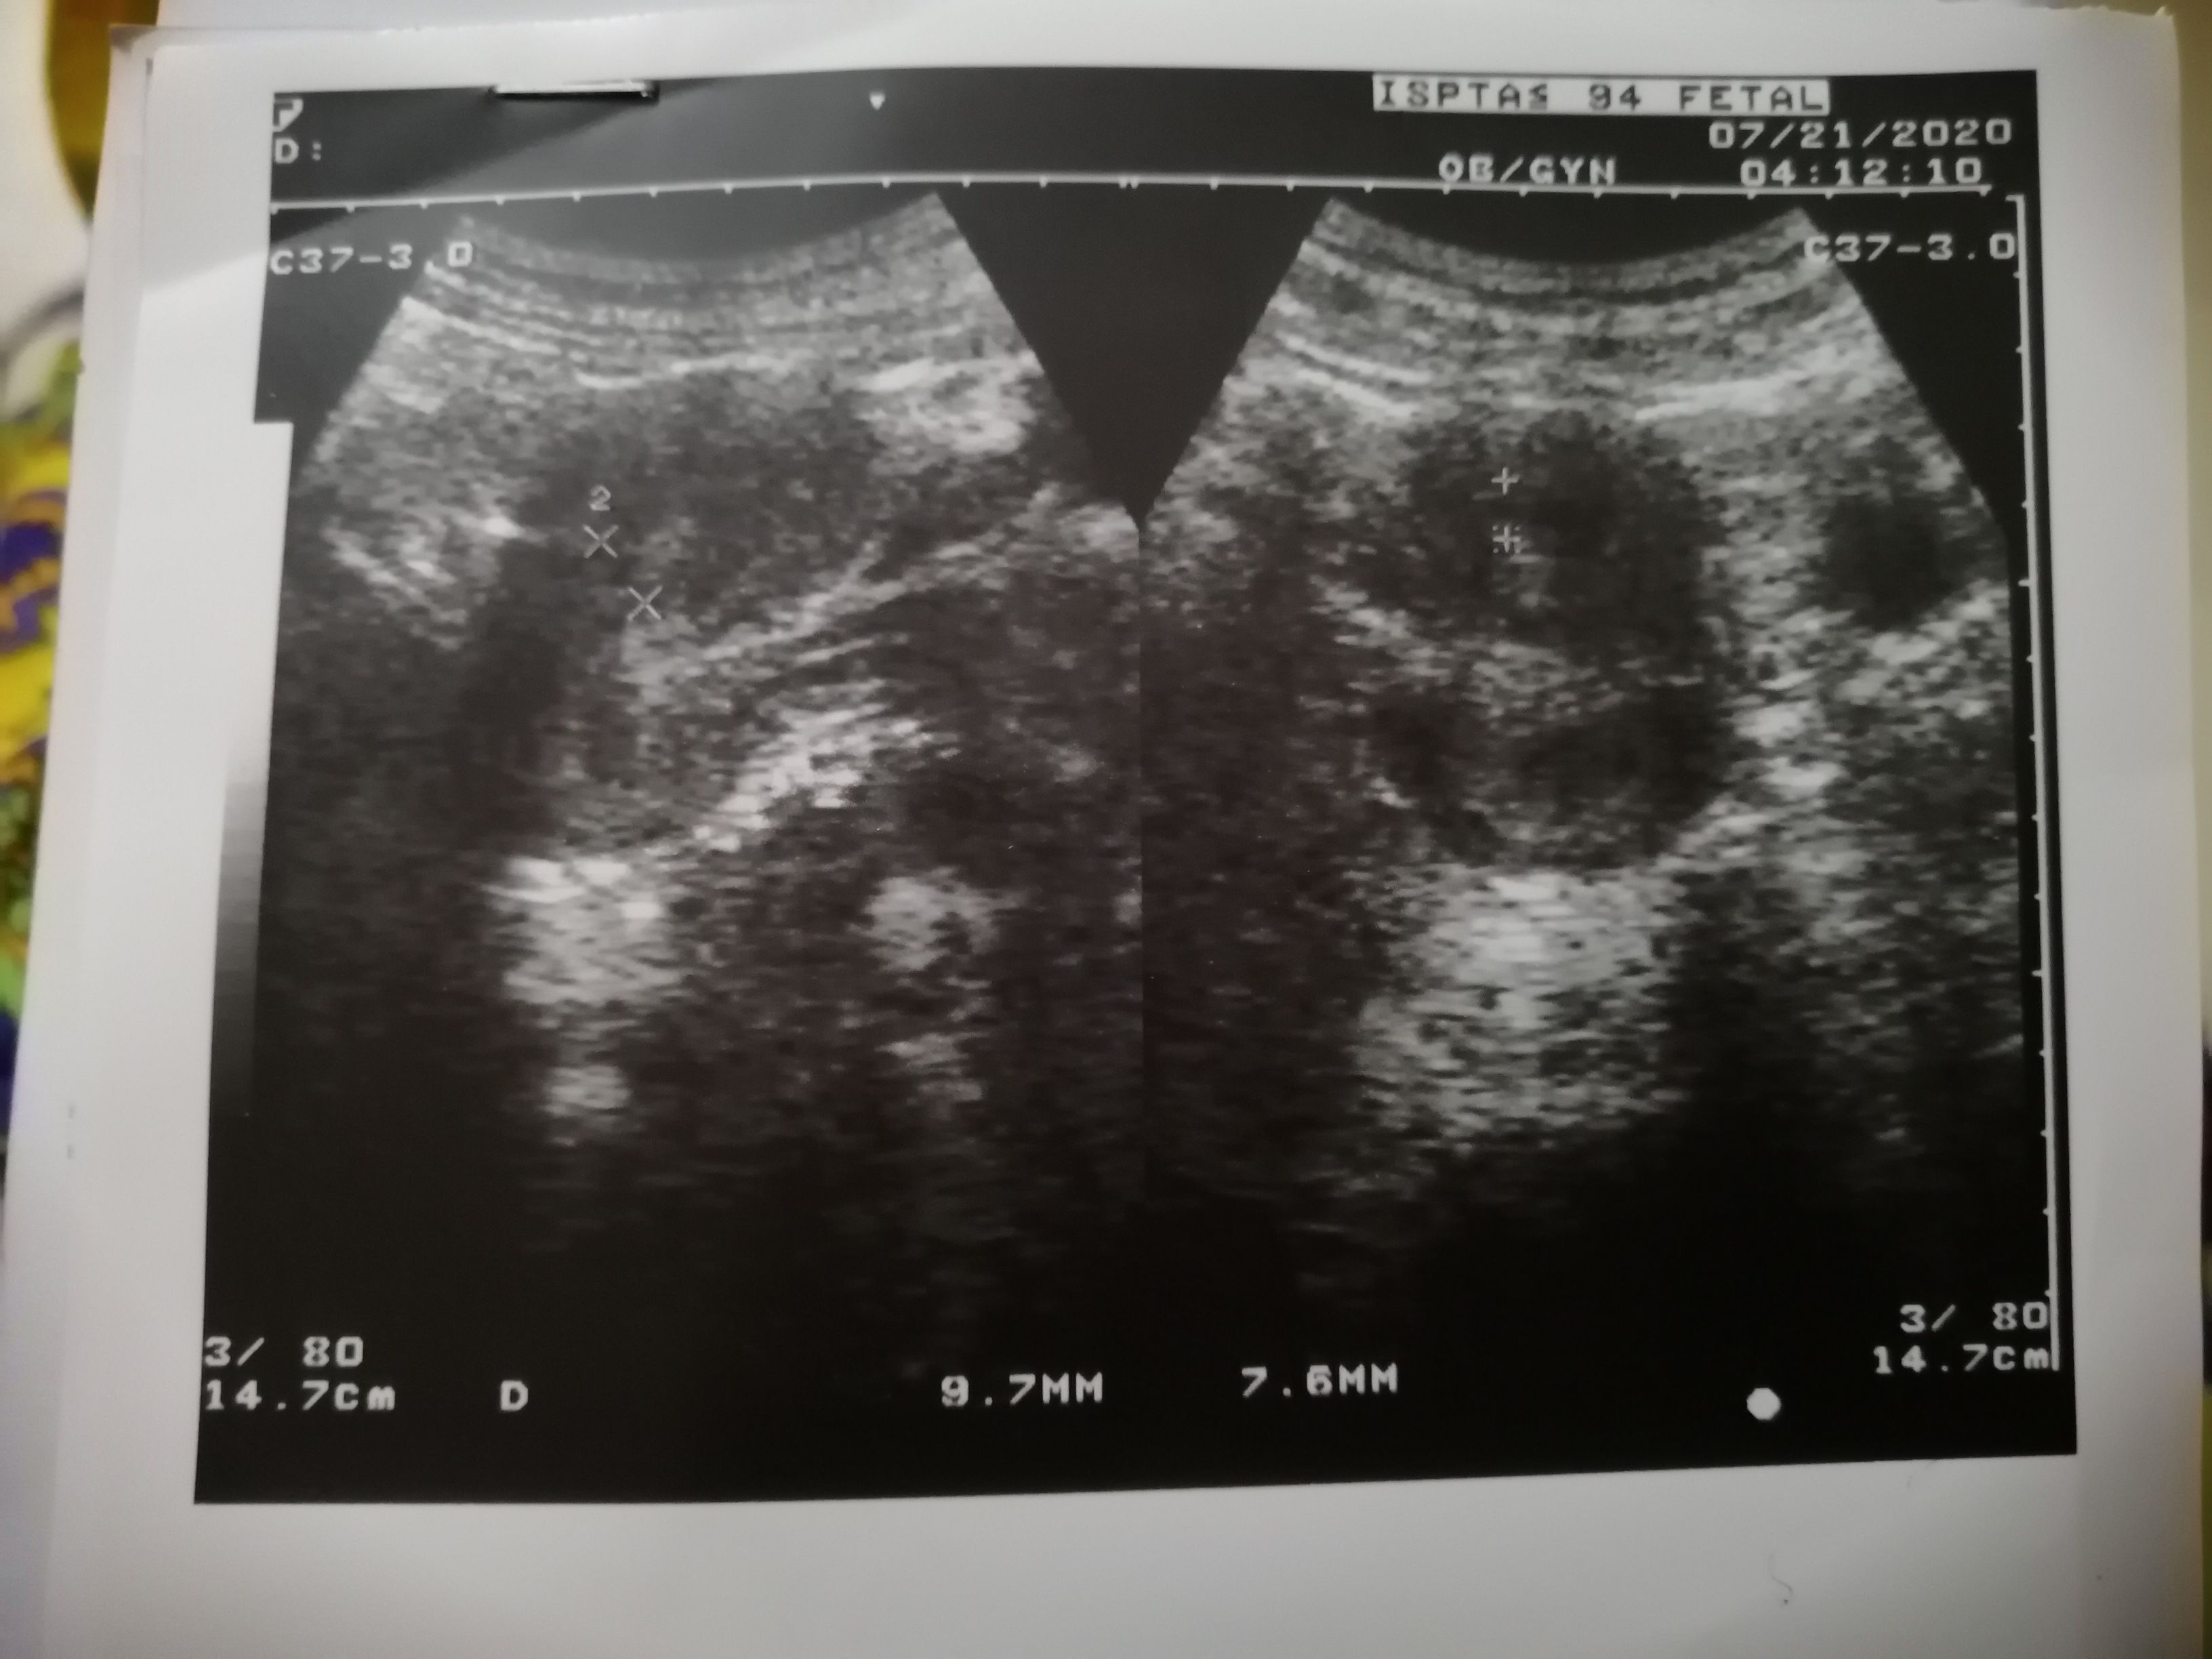

I had a miscarriage in June this year. Is k baad mjhy July and August me timely periods hue but Sept me mjhy periods nhi hue. Strip test negative a rha hai abhi tk. 3 din pehle me apni gynecologist k pas gai jis ne ultrasound kr k btaya k uterus me ek jaga irregular thickness feel ho rhi hai aur lg rha hai jese early gestational sac hai. Duphaston and myfol tablets di hain doctor ne jo me regularly le rhi hun. But me ne aj suba b strip test kiya to wo negative hi a rha hai. Me bht preshan hun k agar pregnancy hai to negative test kyun a rha hai bar bar. Aur agar pregnancy nhi hai to sac kyun nazar a rha hai ultrasound me and me jo medicine le rhi hun us se koi negative effects to nhi hon gy health pe negative pregnancy ki surat me? Please guide I'm so much worried

USG KI REPORT Share krain

Usg report

Medicine theek haan, garri rakhian, rest krain, doctor ki hidayaat py amaal krain early pregnancy USG hy next report ka intizar krna paray ga, wish you good luck